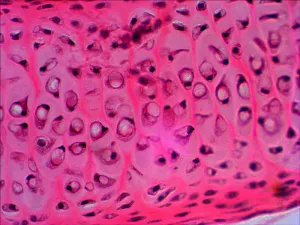

В наборе микропрепаратов:

- Дрозофила (личинка)

- Дрозофила (куколка)

- Дрозофила «норма»

- Животная клетка

- Растительная клетка

- Плесень

- Дробление яйцеклетки

- Митоз в корешке лука

- Поперечно-полосатые мышцы

- Сперматозоиды млекопитающего

- Нерв (поперечный срез)

- Рыхлая соединительная ткань

- Яйцеклетка млекопитающего

- Нервные клетки

- Гиалиновый хрящ

- Гладкие мышцы

- Костная ткань

- Кровь лягушки

- Кровь человека

- Однослойный эпителий

Примеры слайдов под микроскопом смотрите в галерее фотографий, а также в обзоре «Наборы готовых микропрепаратов Levenhuk» на сайте levenhuk.ru.